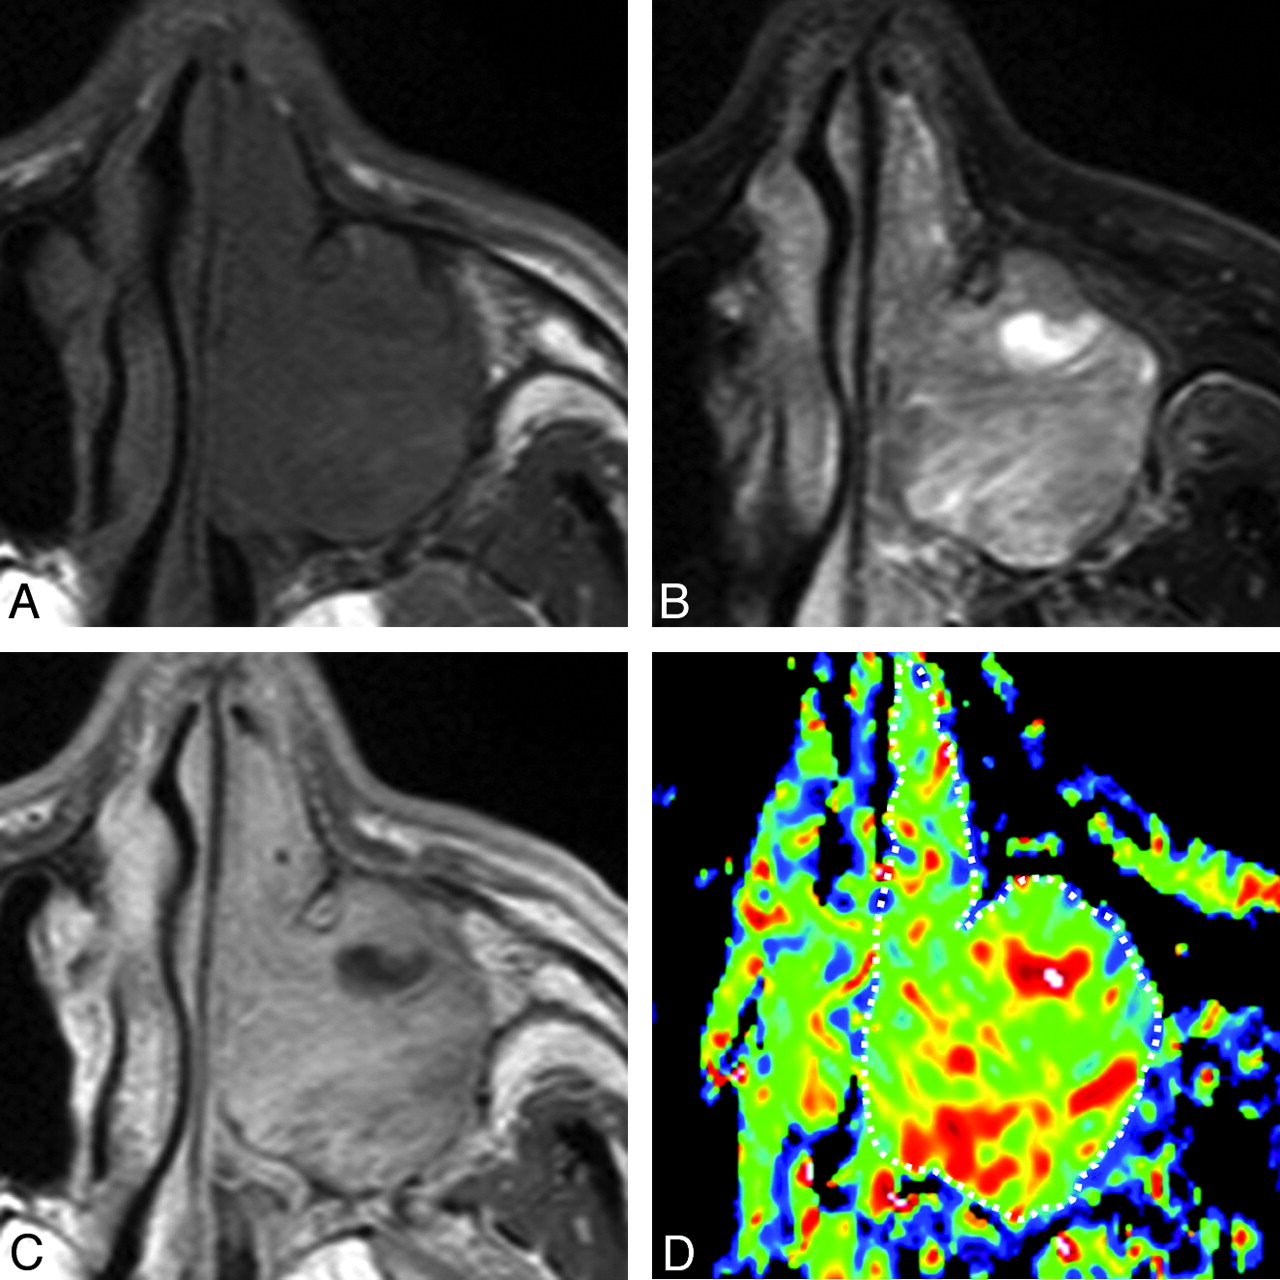

A 69-year-old man with inverted papilloma. A, Axial T1-weighted MR image (TR/TE = 500/15 ms) shows tumor with homogeneous signal intensity filling the left maxillary sinus and nasal cavity. B, Axial FS (SPIR) T2-weighted MR image (TR/TE = 4784 ms/80 ms) shows the tumor with heterogeneous signal intensity. C, Axial CE T1-weighted MR image (TR/TE = 500/15 ms) shows heterogeneously enhanced tumor. D, Axial color ADC map shows tumor with scattered areas of high ADCs. Overall ADC = 1.4 × 10−3 mm2/s. Areas with extremely low, low, intermediate, and high ADCs occupy 0%, 21%, 66%, and 13%, respectively, of the tumor.